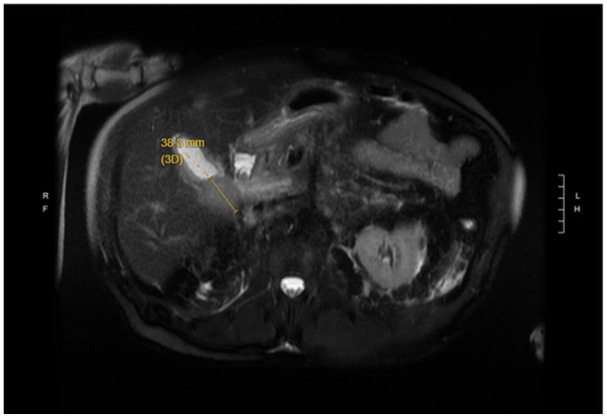

Primary follicular lymphoma (PFL) is an indolent subtype of non-Hodgkin lymphoma that typically involves lymphoid tissues. Gallbladder involvement is exceedingly rare and poses significant diagnostic challenges. Few cases in the literature describe gallbladder follicular lymphoma, particularly in elderly male patients, leaving notable gaps in clinical understanding and management. Herein, we present the case of an 82-year-old male who presented with acute abdominal pain and unintentional weight loss. Initial imaging, including contrast-enhanced computed tomography, ultrasound, and magnetic resonance imaging, revealed a suspicious gallbladder mass with wall thickening and regional lymphadenopathy, raising concern for malignancy. Endoscopic ultrasound-guided fine needle aspiration and subsequent immunophenotyping confirmed a diagnosis of PFL. The patient underwent radical cholecystectomy with lymphadenectomy, and histopathological examination corroborated the diagnosis of gallbladder follicular lymphoma. During follow-up, the patient developed complications, yet no evidence of lymphoma recurrence was observed. A literature review identified 8 similar cases, further emphasizing the rarity of this presentation. Future research should focus on optimizing diagnostic techniques, refining therapeutic strategies, and conducting longer-term follow-up studies to better assess patient outcomes in such a rare disease. This case highlights the need for heightened clinical suspicion and comprehensive evaluation in atypical presentations of extranodal lymphoma.